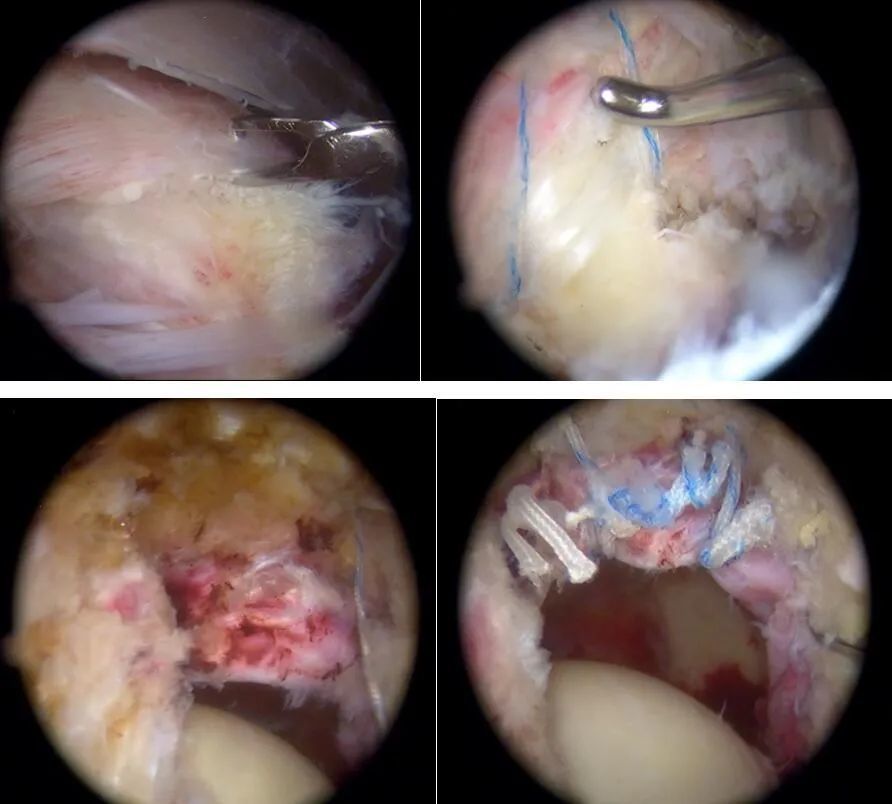

图2 关节镜切口

图3 关节镜下照片

图4 手术照片

决定实施全关节镜下

髋袖损伤和盂唇损伤一期修复

手术由刘建永主刀

顺利完成